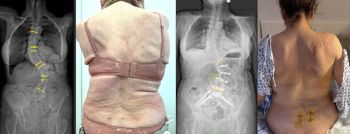

L'equip quirúrgic del Centro Médico Teknon, liderat pel Dr. Christian Morgenstern, director del Morgenstern Institute of Spine al Centro Médico Teknon, ha intervingut amb èxit una pacient de 80 anys afectada per una escoliosi degenerativa dorsolumbar severa. El cas, que presentava una curvatura de 57º a la zona lumbar i 42º a la dorsal, ha estat resolt mitjançant la tècnica ACR (correcció de columna anterior) en dos temps.

La intervenció es va dividir en dos temps quirúrgics per maximitzar la seguretat. En una primera fase, es van realitzar abordatges mínimament invasius per via anterior i lateral per rectificar parcialment la columna, per la qual cosa es va aconseguir reduir la corba lumbar de 56 º a 39 º de forma immediata. Aquesta correcció prèvia va permetre que la segona fase, realitzada per via posterior, fos molt menys agressiva i es pogués executar de forma percutània.